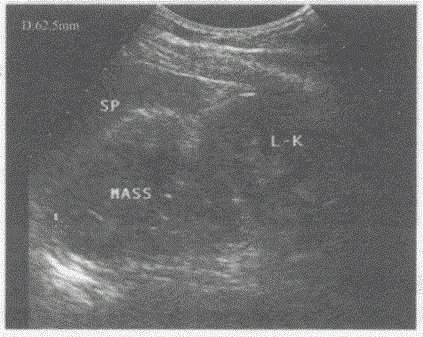

问题 临床资料:男,55岁,肺癌手术后2年余。 超声综合描述:左肾上腺区可见6.3cm×3.2cm形态不规则低回声,内回声不均,边界尚清晰,左肾受其挤压失常态。 超声提示:

选项 A.肝右叶实性占位 B.左肾癌 C.右肾上腺区实性占位(嗜铬细胞瘤) D.左肾上腺区实性占位(转移癌)

答案 D